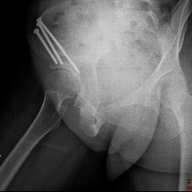

• NUEVA RX

Hola de nuevo a todos!!! Como siempre os digo, lo siento por no tener esto más al día pero, a parte de no tener mucho que contar, estoy a tope de trabajo, mañana y tarde y me es muy complicado llevarlo todo!!!! Como bien sabéis, la cadera que me operé primero, había empezado a darme… Leer más